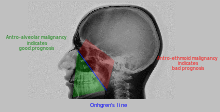

| Malignancy |

![]() Onhgren's line